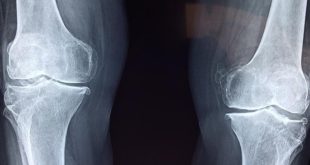

Titulek je samozřejmě míněn jako nadsázka. Nejde teď o to, že by genetické faktory stály za tím, s jakou pravděpodobností člověk skončí s umělých kloubem (takové faktory jistě existují, ovlivňují sklon k artritidě, úrazům, výsledkům úrazů, ale člověk se také musí do daného věku vůbec dožít), ale o výsledek chirurgického …